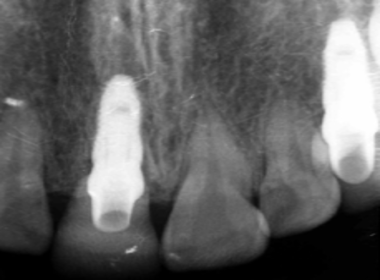

| 0709 #36#37 左下第一第二大臼齒 |

![]() |